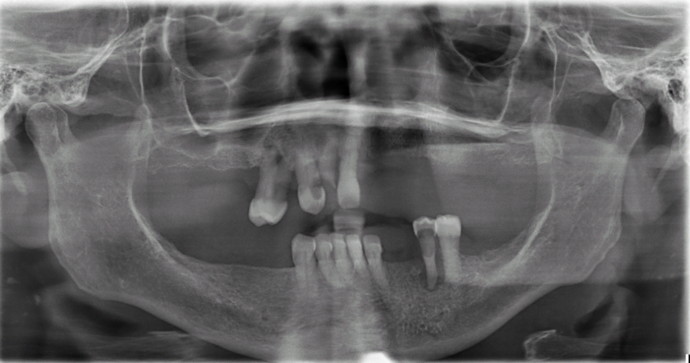

Patient had severe gum disease and she started losing her teeth one by one and was very unhappy with her partials. Patient was holding on to the very last few teeth in her mouth which were loose, in order to avoid wearing dentures! When she discovered Dr Bidra, and was informed that she could get transformed in one single day, she and her husband were immediately motivated. Patient had her teeth extracted, implants placed and new teeth installed all in one day.

Procedures : extractions, implants, All on 4 , Teeth in a day, no bone grafting and full mouth reconstruction with monolithic zirconia bridges.